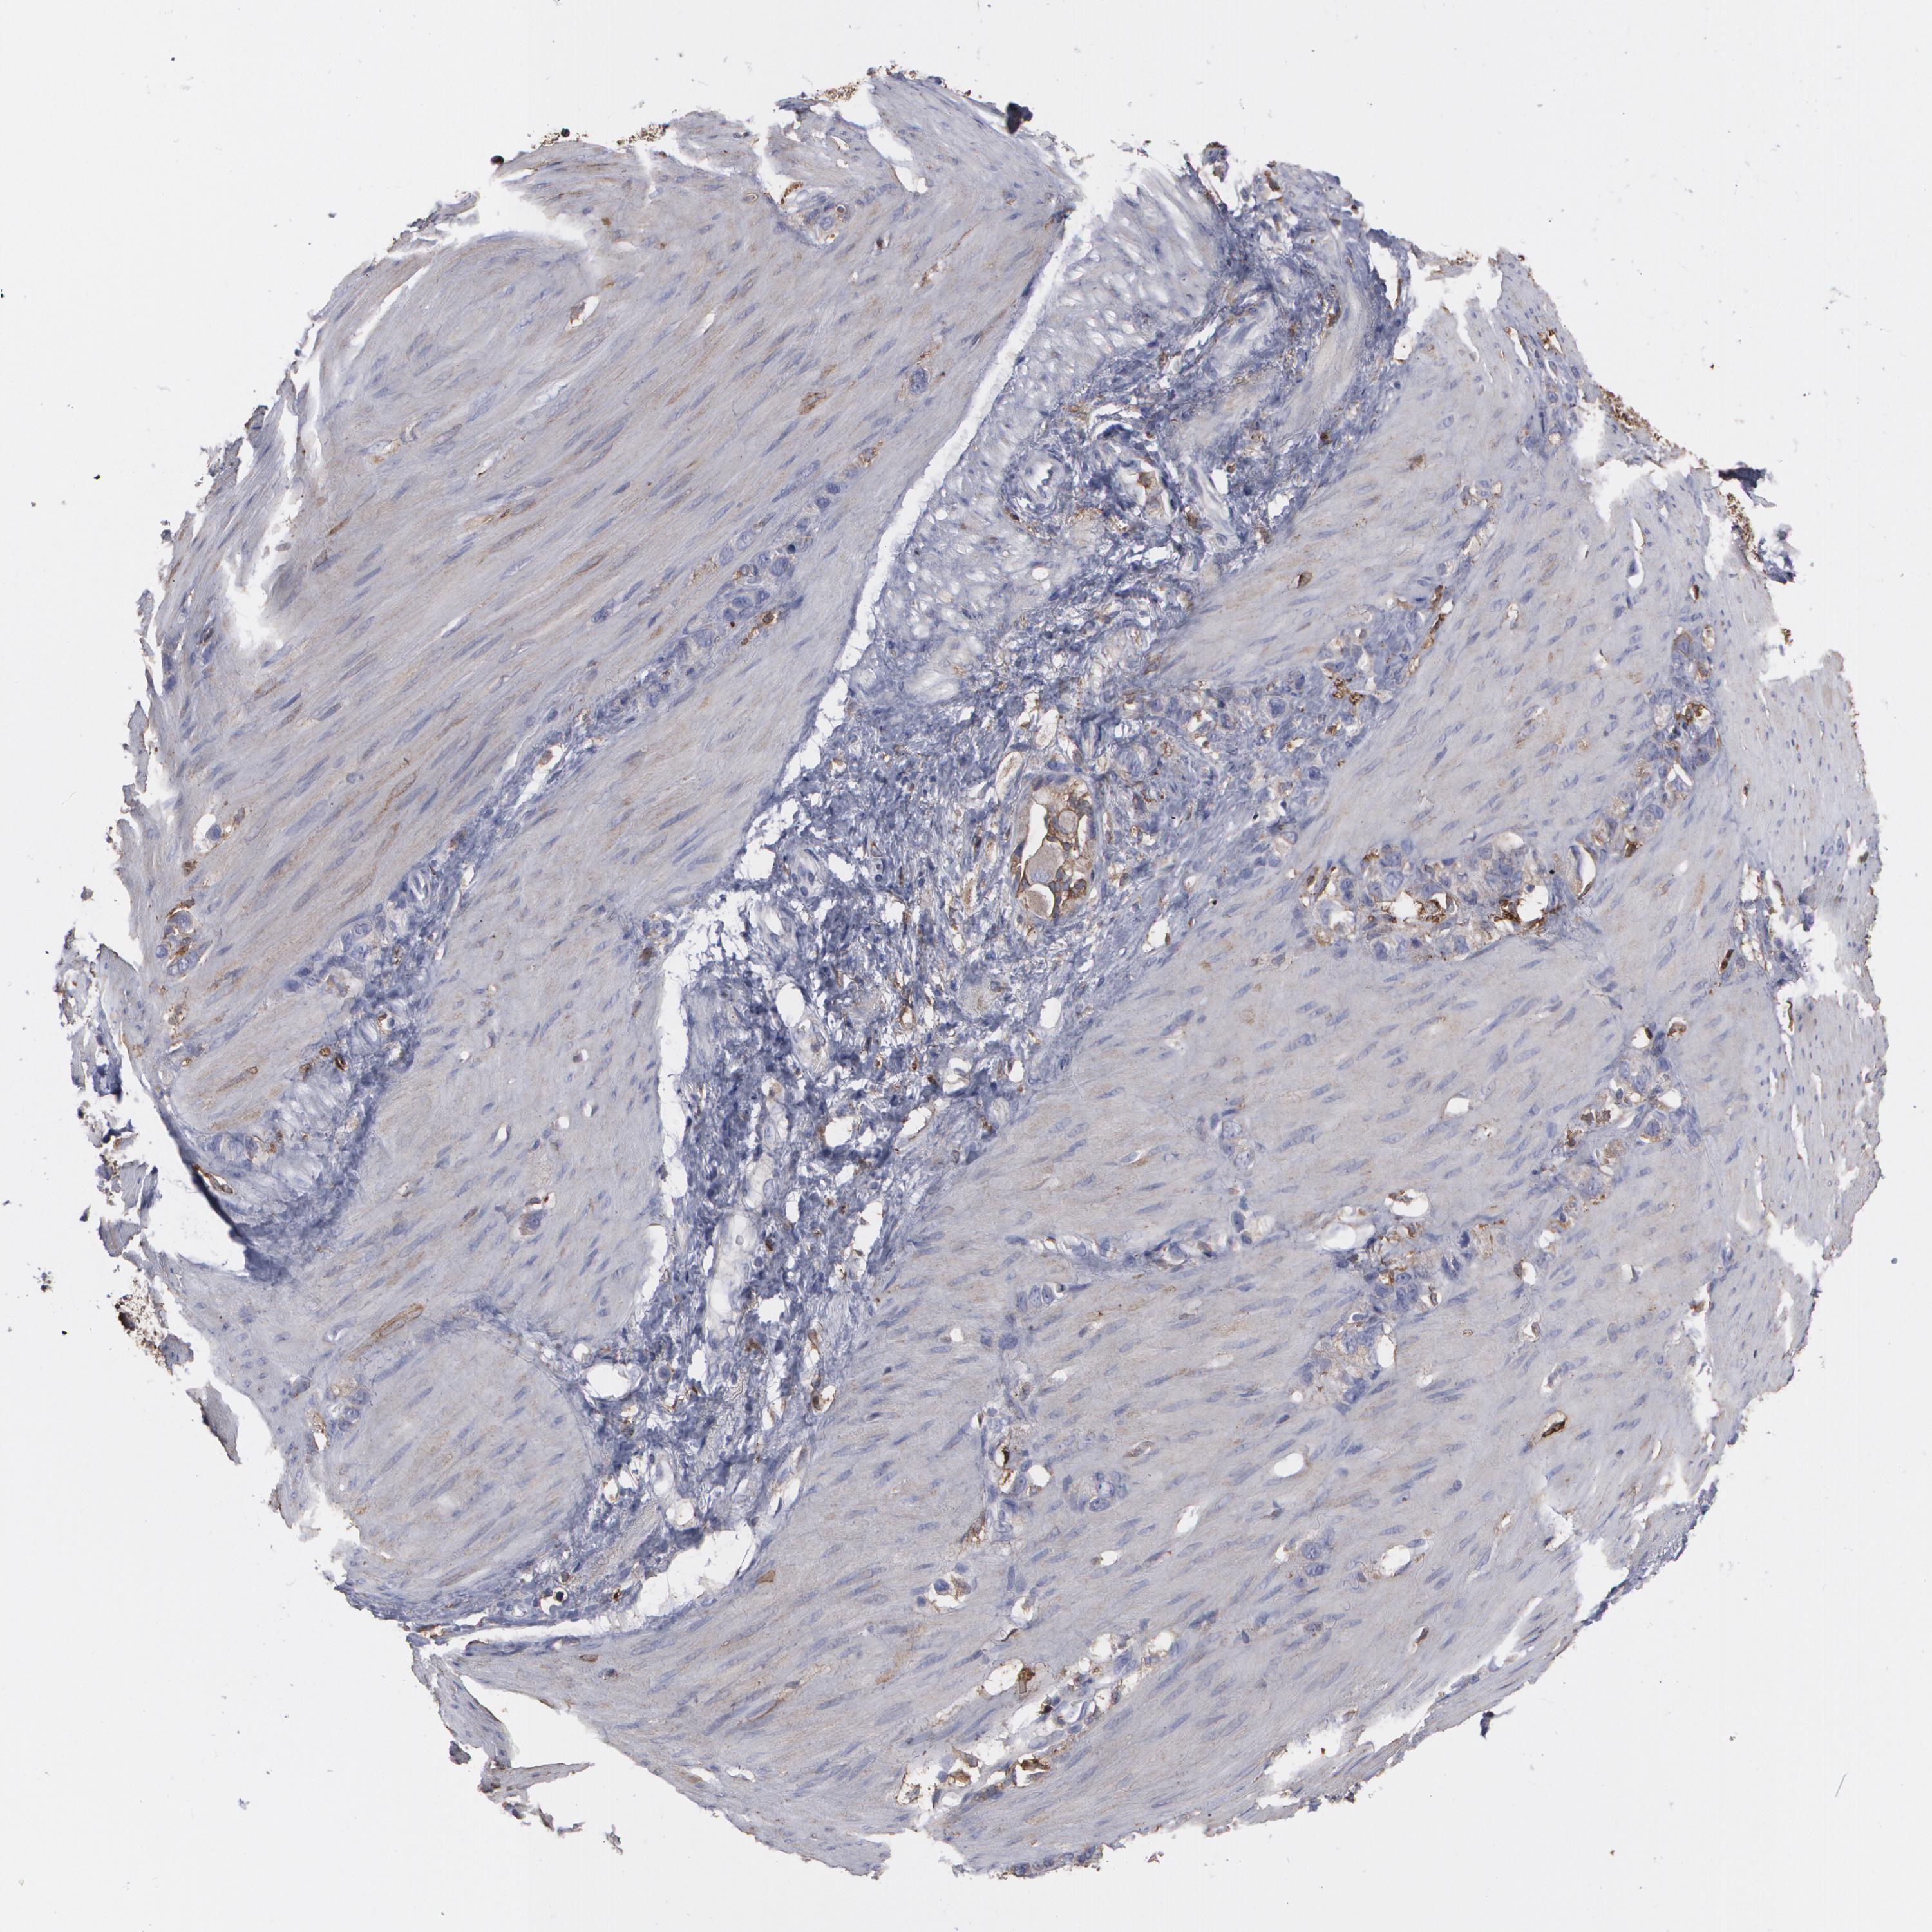

STOMACH CANCER - Protein expressioni

A mouse-over function shows sample information and annotation data. Click on an image to view it in a full screen mode. Samples can be filtered based on level of antibody staining by selecting one or several of the following categories: high, medium, low and not detected. The assay and annotation is described here.

Note that samples used for immunohistochemistry by the Human Protein Atlas do not correspond to samples in the TCGA dataset.

Antibody stainingi

Antibody staining in the annotated cell types in the current human tissue is reported as not detected, low, medium, or high, based on conventional immunohistochemistry profiling in selected tissues. This score is based on the combination of the staining intensity and fraction of stained cells.

Each image is clickable and will lead to virtual microscopy that enables deeper exploration of all samples and also displays staining intensity scores, fraction scores and subcellular localization as well as patient and tissue information for each sample.

Antibody HPA001536

Antibody CAB035996

Staining

High

Medium

Low

Not detected

Intensity

Strong

Moderate

Weak

Negative

Quantity

>75%

75%-25%

<25%

None

Location

Nuclear

Cytoplasmic/membranous

Cytoplasmic/membranous,nuclear

Adenocarcinoma, NOS

Adenocarcinoma, High grade